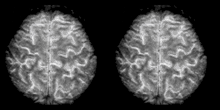

Cognitive neuroscience aims to reduce cognition to its neural basis using new technologies such as fMRI, repetitive transcranial magnetic stimulation (rTMS) and Magnetoencephalography (MEG) as well as older methods such as Positron emission tomography (PET) and Electroencephalography (EEG) studies. Due to the correlational designs used in fMRI, many scientists have coined this up and coming field as the new phrenology in the sense that techniques such as fMRI rely heavily on complex statistics.[17] Type 1 errors can lead scientists to draw premature and incorrect causal relationships if improper designs are used.[18]